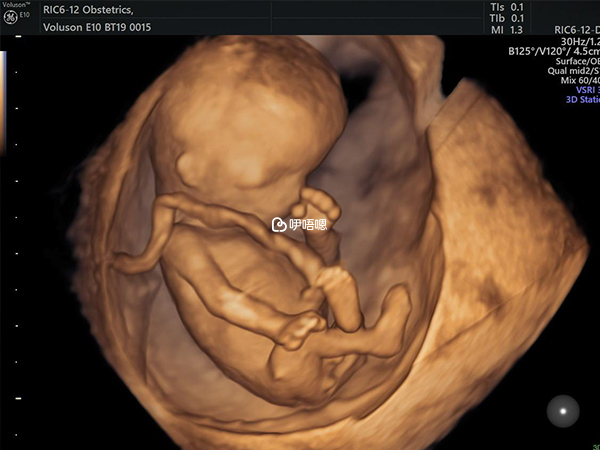

我第八天時測都是大白板,還有人是有肚子疼針扎感覺說是胚胎著床,以及會有著床血,這些反應我都沒有,所以姐妹們移植後還是要放寬心。不要和別人對比症狀,因為每個人的體質本來就不一樣,我是第十一天才測出雙槓的。人生第一次看見雙槓,當時別提有多高興了。第十四天抽血的時候hcg值四百多,第二十一天是一萬兩千多。後來試管畢業去建檔醫院做NT看到寶寶B超圖時,激動的眼淚都流出來了。